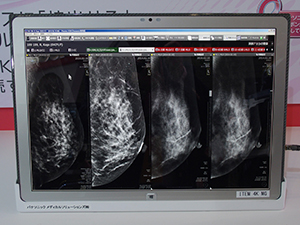

新製品のPlissimo MCは,4Kタブレットの「タフパッド 4K UT-MA6」をPlissimo MGなどのマンモグラフィ診断用のワークステーションに接続して,DICOM Q/Rによって画像を取得する。タフパッド 4K UT-MA6には,ビューワソフトウエアがインストールされており,取得した画像を参照できるようになっている。このため,新たにソフトウエアを追加する必要はない。タフパッド 4K UT-MA6は,20型モニタというワイドサイズでありながら,重量は2.54kgという軽量化を実現しており,無線LAN環境が整った施設であれば,どこでもすぐにカンファレンスを行える。さらに,4Kテレビや4KモニタとMini DisplayPortケーブルで接続すると,タブレットの画像をさらに大画面で観察できるようになる。ブース内では,タフパッド 4K UT-MA6と「VIERA」ブランドの4Kテレビとを接続しプレゼンテーションを行っていた。

従来のカンファレンスは,プロジェクタを用いることなどにより,高精細のマンモグラフィ画像を高画質のままで観察することが困難であった。また,ワークステーションとプロジェクタの接続ができないといった問題もあった。Plissimo MCはこうした問題を解決し,効率的なカンファレンスを可能にする。なお,Plissimo MCはDICOM規格対応なので,マンモグラフィに限らず,CT,MR画像を用いたカンファレンスも行える。

4Kタブレットと接続して「VIERA」の4Kテレビに表示 |